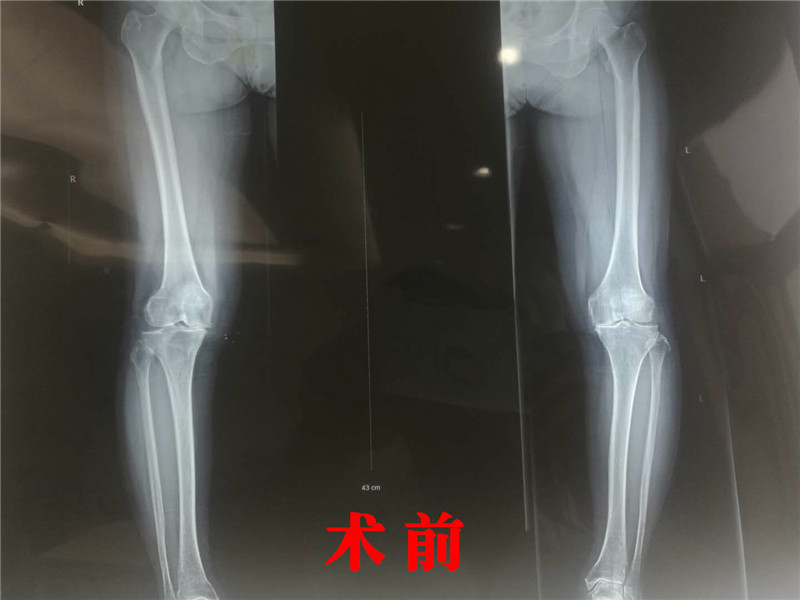

5月,我院骨科成功实施全区首例双膝关节同期置换术,填补了全区在该技术领域治疗的空白。患者葛某,是一位64岁的老太太,双侧膝关节疼痛10余年,屈曲畸形。每逢天气变化,上下楼梯、久坐后起身时就会疼痛难忍,苦不堪言。近来症状持续加重,无法站立行走,甚至夜间床上翻身也出现双膝关节疼痛,口服药物等保守治疗无效,严重影响了患者的生活。老太太辗转了多家医院,均建议行全膝关节置换,当听说我院与东南大学附属中大医院深度合作以后,引进了大量博士等高层次人才,骨科执行主任吴战坡博士师从张英泽院士,在骨关节领域造诣颇深,擅长膝、髋、肩关节置换,因此慕名而来。经过吴战坡主任检查后确诊为双膝骨关节炎,需进行双侧全膝关节置换手术。 以往,这样的大手术一般是分期、分侧手术,双侧置换同期进行风险高,通常需转上级医院才能进行。骨科专家吴战坡在详细了解患者病情并仔细检查评估后,决定为患者同期实施双侧关节置换手术。由于这是我院首例同期双膝关节置换术,院部高度重视,高增鑫副院长亲自主持全科医师进行术前讨论,保证了手术的顺利开展。 2019年5月4日,吴战坡主任医师带领诊疗组成员赵晓明、陆海涛主治医师、杨海源住院医师成功为该患者实施双膝关节置换术。手术按照计划顺利地完成,效果显著,术后第一天即恢复了膝关节的主动活动,术后第三天就能借助助行器下地行走。老太太解除了病痛,心情高兴极了,对吴战坡主任连连翘起大拇指。目前,老人恢复良好,正在按医生制定的方案进行康复训练。 人工膝关节置换手术是由于正常膝关节解剖结构被严重破坏,发生严重的疼痛,不能正常的生活和工作,医生通过外科手术的方法去除损坏的关节,把经过精密设计和制造的人工膝关节来替换原来的膝关节手术方法。人工膝关节置换术目前已成为治疗膝关节疾病的重要手段之一,但是这类手术等级高、难度大、技术要求高,双膝关节同期置换更是难上加难,以前从未在溧水地区开展过。本例手术的成功实施,不仅标志着我院在该领域取得了实质性突破,也结束了溧水地区患者双膝不能同期置换的历史。随着高层人才的引进,随着技术水平和服务能力的提高,溧水老百姓在家门口就享受到了高级专家的诊疗服务。